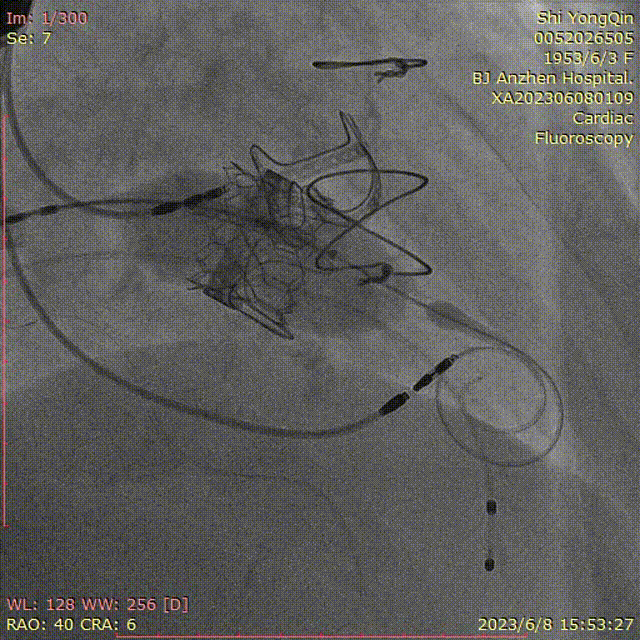

患者全麻,摆体位可寻找衰败生物瓣的切线投照体位,后消毒铺巾,穿刺双侧股静脉,左侧股静脉植入临时起搏器,右侧股静脉作为主入路,在超声指引下,按术前CT评估要求穿刺房间隔到达左心房,肝素化后(ACT>250秒),导入Agilis可调弯鞘管到达左心房,Pig造影导管跨过二尖瓣到达左心室心尖部,导入Safari导丝到达左心室;以12×40mm球囊扩张房间隔确认SAPIEN 3瓣膜可通过后,导入反向安装的23mm+3ml瓣膜到达下腔静脉,组装成功后,翻转其调弯系统后送入到左心房,跨过衰败的二尖瓣,在切线投照体位定位精确后,快速心室起搏下释放瓣膜,见瓣膜位置良好,超声显示无瓣周漏,测量左心室和桡动脉压差稍增高,超声显示LVOT流速稍增快;撤出瓣膜输送系统及导丝,撤出临时起搏电极,局部加压包扎,患者清醒后安返病房。

瓣膜导入

瓣膜的定位及释放